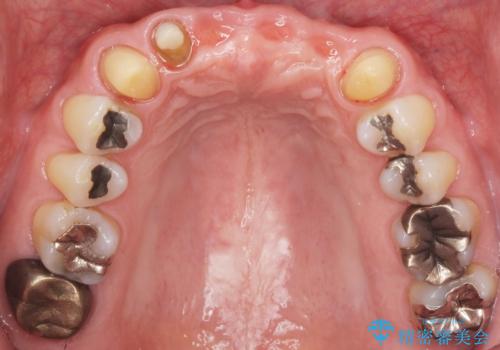

左上の側切歯(左上2)を抜去し、右上の側切歯(右上2)の再根管治療後、セラミックのブリッジによる補綴を行いました。

- ¥770,000 (根管治療×1本、土台×1本、仮歯×6本、クラウン×6本)費用は治療当時の料金となります

クラウンの種類:オールセラミッククラウン スタンダード